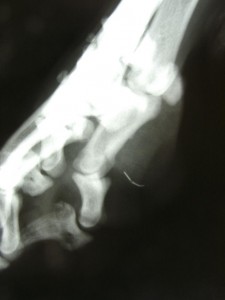

Die Suche nach einem Fremdkörper kann die sprichwörtliche Suche nach der “Nadel im Heuhaufen” werden. Die Bilder zeigen wie hilfreich der C-Bogen hierbei ist. Für den Patienten ist diese Art der Suche deutlich Gewebe-schonender.